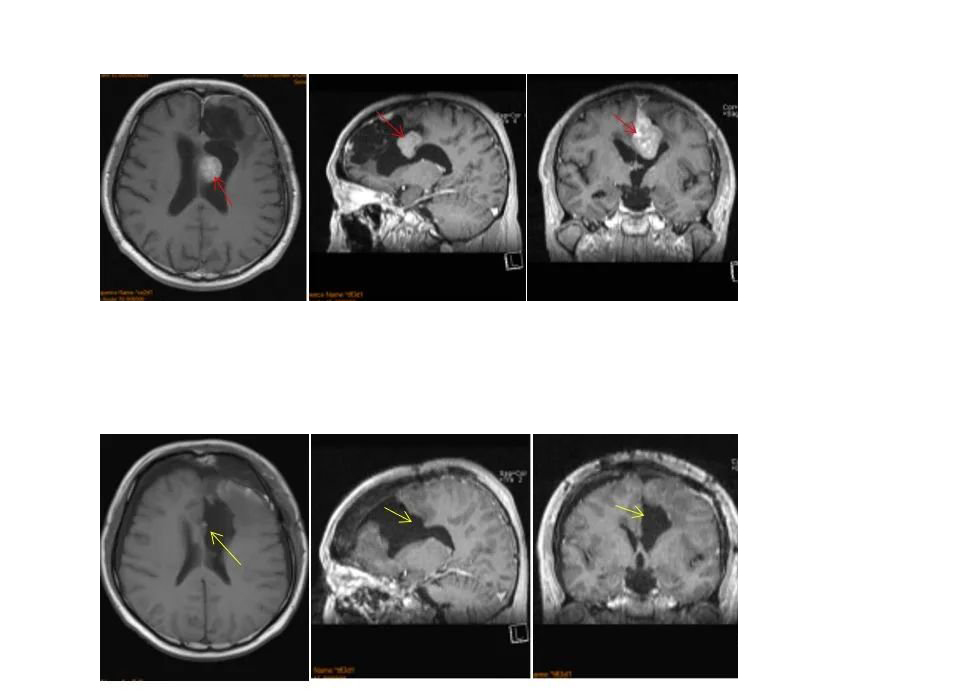

病情回顾:四十多岁赵先生因突发癫痫就医,家人带其MRI检查后发现大脑左额镰旁脑膜瘤,立即在国内某医院进行部分切除。术后需要反复伽马刀治疗,没想到3年后脑膜瘤恶化复发为多发脑膜瘤,复查核磁显示大脑镰前段基本均受累,并有大脑镰右侧肿瘤生长,矢状窦被累及,左侧额部凸面硬脑膜多处肿瘤生长。

在术中iMRI、术中神经导航等国内少有的高科技复杂仪器辅助下,巴特朗菲教授为赵先生实施了手术,大脑镰旁及矢状窦旁的肿瘤被完全切除,并地保护了正常的脑组织结构。赵先生术后二天下床进行康复锻炼。神经功能无任何异常,术后13天步行出院。

赵先生术前术后MR对比